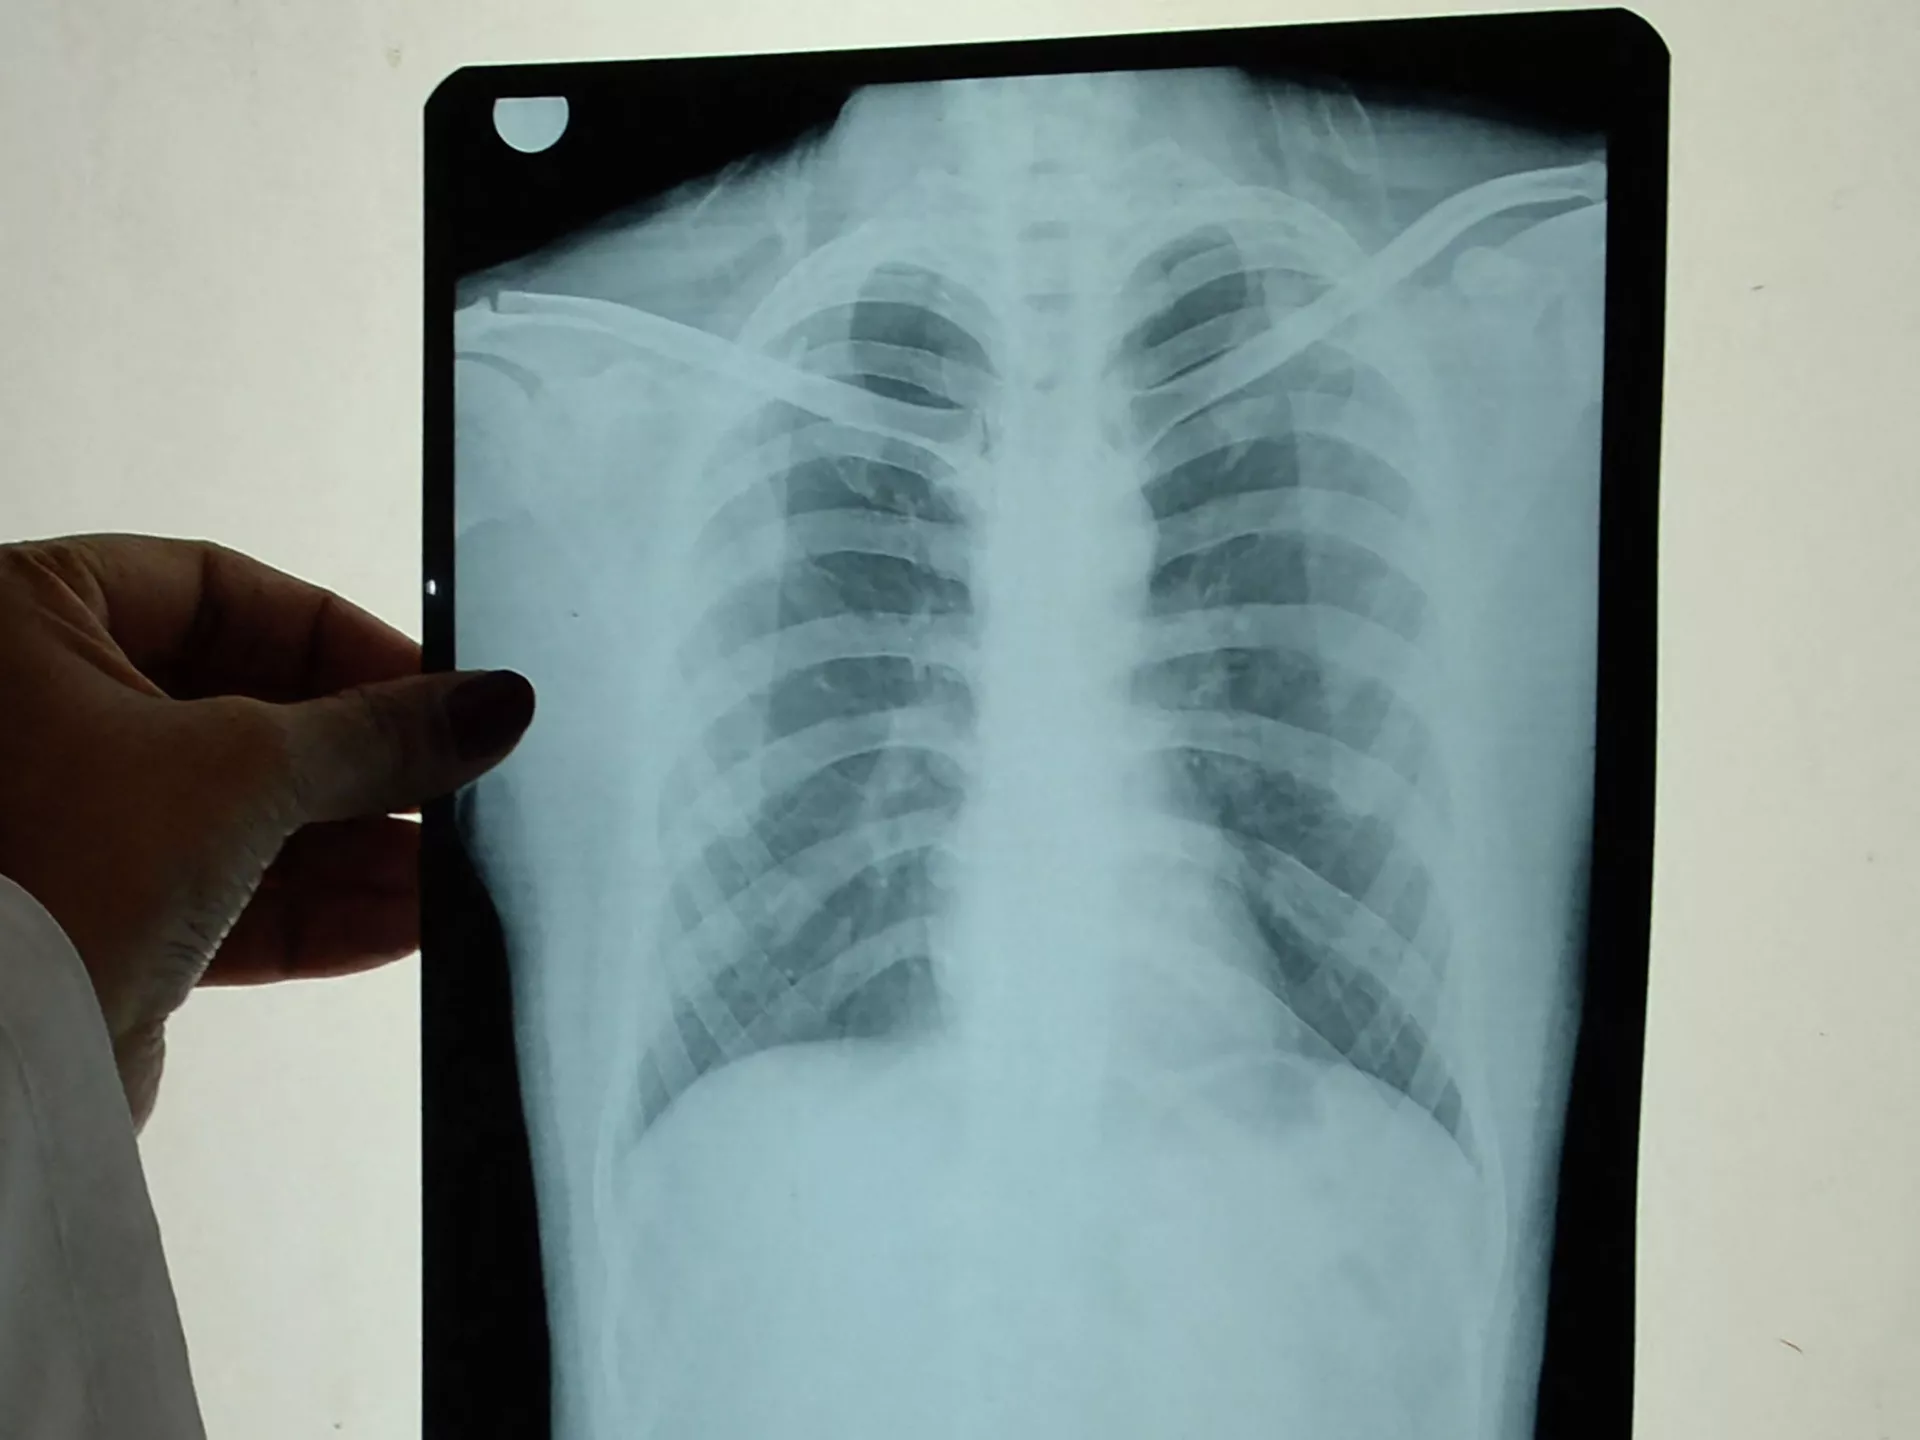

— Биринчи эле какырык тапшырат. Ал бардык аймакта бекер жасалат. Экинчиден, өпкөсүн рентгенге тарттырат. Ушул эки жолу менен эле аныктап коёт.